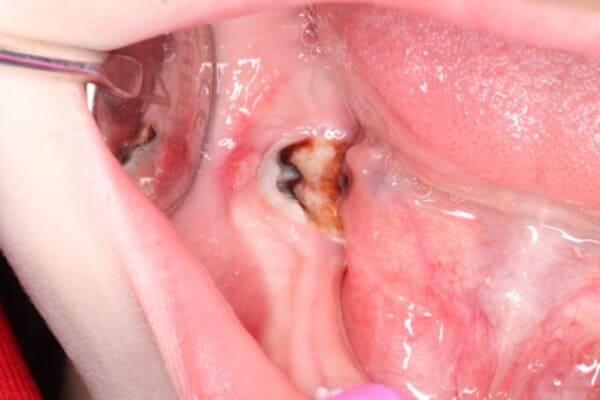

Проблема виникає, коли нерв (пульпа) постійного зуба передчасно гине від травми чи інфекції. Це критично, адже саме пульпа відповідає за ріст кореня. Без неї корінь залишається коротким і тонким. Такий зуб не може витримувати жувальне навантаження і ризикує бути втраченим. Це як дерево з великою кроною та маленьким корінцем: найменший вітер може його вирвати.

Завдяки науковим дослідженням ми знаємо, що навколо кореня зуба є стовбурові клітини. Наша методика дозволяє створити в зубі спеціальні умови, щоб ці стовбурові клітини мігрували в кореневий канал. Там вони перетворюються на клітини, схожі на клітини пульпи, і відновлюють ріст кореня — як у довжину, так і в товщину.